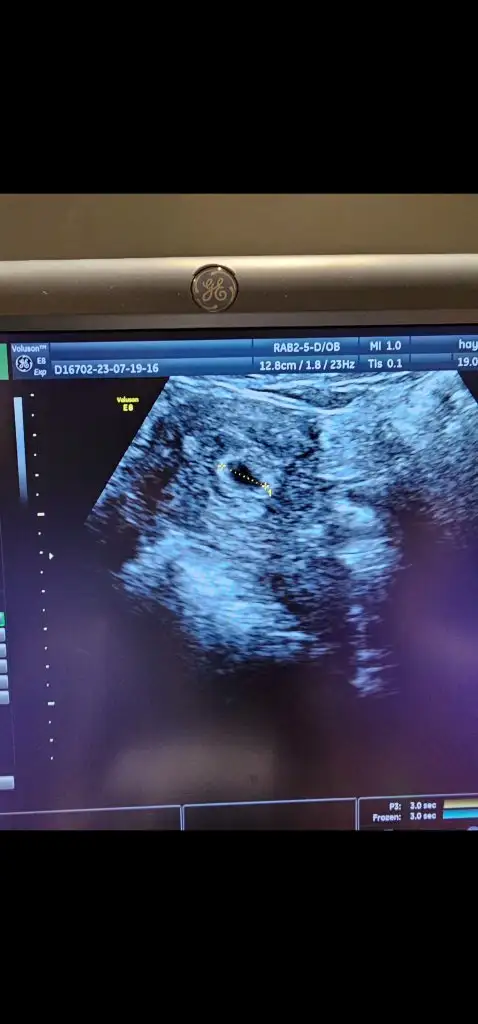

Bizde salı günü gittik sana yazmayı unuttum heycandanMerhaba hanımlar, dün akşam biraz kanamam oldu alelacele doktora gittik o sıra keseyi de görmüş olduk çok şükür. Biraz riskli geçiyor gebeliğim. Normal mi bu sizce. Bir de cinsiyet için çok erken ama sizce kese neye benziyor

Ayyy çok sevindim, çok güzel bir haber bu. Rabbım kucağımıza almayı nasip etsin inşallahBizde salı günü gittik sana yazmayı unuttum heycandan6+1 di Salı günü ve keseyi gördük kalp atışını duyduk çok şükür ben keseden cinsyeti pek anlamam açıkçası keseyi görmene çok sevındım daha da sağlıklı haberler alırız inşallah